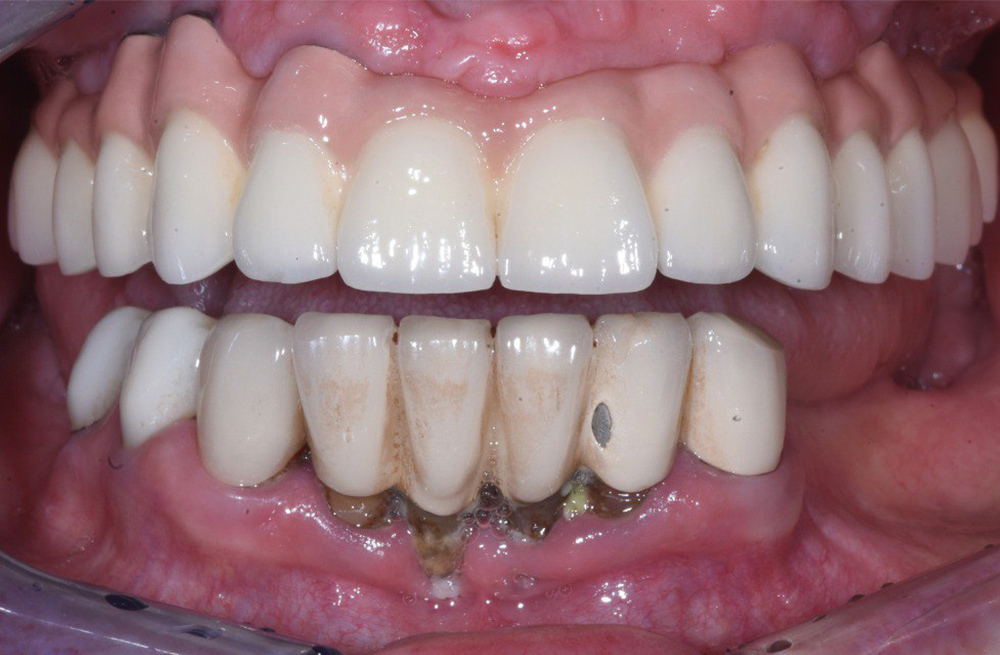

Тотальная реабилитация пациента с ятрогенными поражениями корней по схеме 6 на 6 и надёжной балочной конструкции